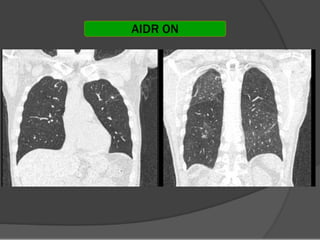

TECNICA DE BAJA DOSIS YTECNICA DE BAJA DOSIS Y

ALTA RESOLUCIONALTA RESOLUCION

Se realizan cortes finos de 1 mm de grosor aSe realizan cortes finos de 1 mm de grosor a

intervalos de 10 mm para el estudio inicial y cortesintervalos de 10 mm para el estudio inicial y cortes

de 1 mm a intervalo de 20 mm para el seguimientode 1 mm a intervalo de 20 mm para el seguimiento

de la patología pulmonar crónicade la patología pulmonar crónica

En el caso de los prematuros, la secuencia es deEn el caso de los prematuros, la secuencia es de

cortes de 1 mm cada 5 mm debido al pequeñocortes de 1 mm cada 5 mm debido al pequeño

tamaño del tórax.tamaño del tórax.

Neumol Pediatr 2015; 10 (2): 67 - 71Neumol Pediatr 2015; 10 (2): 67 - 71